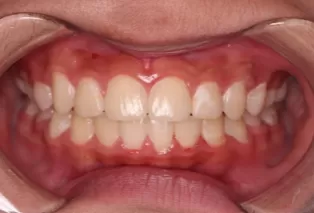

Intraoral photos